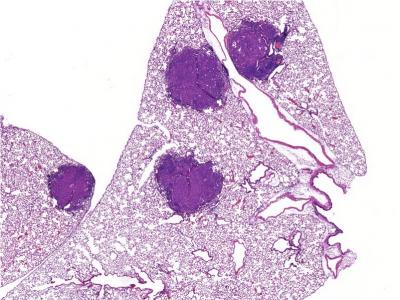

The lab of Salk Professor Reuben Shaw showed that late-stage cancers can trigger AMPK's cellular recycling signal to cannibalize pieces of the cell, supplying large lung tumors with the nutrients they need to grow. The work, which appeared in Cell Metabolism on November 8, 2018, suggests that blocking AMPK in some conditions could stop the growth of advanced tumors in the most common type of lung cancer.

But the Shaw lab's new work suggests that AMPK actually helps large tumors grow. In the current study, the team observed groups of mice with and without the AMPK fuel gauge to see how tumors developed.

The team analyzed which genes in tumor cells from the same mouse models were being activated under various conditions. One gene that was particularly active was Tfe3, which is known to activate cellular recycling. It turned out that when tumors became large enough that cells in the middle were too far from easy access to nutrients, AMPK signaled Tfe3 to initiate recycling of cellular materials as nutrients--effectively cannibalizing pieces of the cell--for the tumor to use.